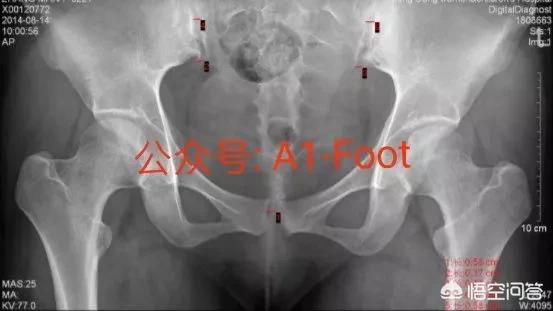

WeChatの公開番号A1-Footをフォローし、オリジナルの科学論文「Neglected Maternal Pubic Bone Separation Pain」を読む。

「恥骨結合裂」は妊娠合併症の一つであり、母体の外科疾患、周産期罹患の一つである。外国における有病率は1:300~1:3000であり、恥骨結合裂隙の拡大は早くても妊娠10週前後で起こり、出産予定日付近でピークに達する。恥骨結合は妊婦に大きな痛みをもたらし、治療が間に合わなければ、その症状は8週間以上続くこともある。陣痛中、恥骨結合の痛みは妊婦の動きを制限し、妊婦の健康と胎児の子宮内発育に悪影響を及ぼします。陣痛中は、陣痛の進行に影響を及ぼし、陣痛の停滞や帝王切開率の上昇を招きます。産褥期には状態が悪化し、母体の回復に影響を及ぼし、動きが制限され、ひどい場合には尿失禁、尿漏れ、子宮脱を引き起こすだけでなく、興奮しやすく抑うつ状態になりやすく、産後うつ病の発症率が高まる。

恥骨結合離開の診断:

産前または産後の母体の恥骨結合の激痛、活動性、悪化するとひっくり返る、腰仙痛や下肢痛と組み合わせることができる; ②いくつかの歩行障害、歩行アヒルステップ; ③患者の一部が腰背部、鼠径部の痛みに現れた; ④身体検査の恥骨結合は明らかな圧力と痛みであり、骨盤圧迫-分離テストが陽性であり、恥骨結合のギャップを広げるために触れることができる; ⑤出生前の超音波検査または出生後のDRとCTは、恥骨結合の分離面の幅が10ミリメートル以上であることを示している。出生前超音波検査または出生後DRとCTで恥骨結合が分離しており、分離面の幅が10mm以上である。

罹患の原因:

仙腸関節周囲の靭帯と恥骨結合は、妊娠中のホルモンレベル、陣痛障害、出生後の体位変換障害、スポーツ障害などの多因子的な影響を受けて弛緩し、恥骨結合の過度の分離と仙腸関節の亜脱臼を誘発する。

治療だ:

出生前の恥骨結合離開の患者には、医師の指導の下、綿密な経過観察、労作を避け、科学的に分娩様式を選択し、分娩後に適時に積極的に介入・治療することをお勧めします。出生後の恥骨結合離開の患者には、早期に骨盤バンドを交差させた操作修復+外固定を行うことをお勧めします。これにより、速やかに痛みを和らげ、患者の回復時間を大幅に短縮することができます。患者は発症後、安静をとることを勧められる。さらに、骨盤底リハビリテーション療法、鍼治療、局所閉鎖療法なども治療の補完となる。

予後:

早期の介入と治療は一般的に有効であるが、骨盤底臓器脱とストレス性尿失禁を合併している患者もおり、専門医の診察とフォローアップが必要である。

次の産後の恥骨離開の患者は、早期の骨盤バンドによる体位変換と外固定で安定し、回復に成功した。